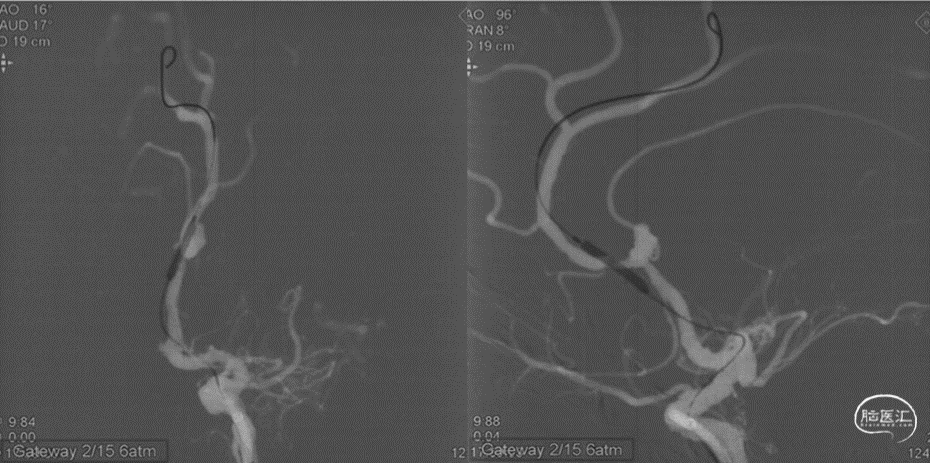

远端小血管动脉瘤是介入治疗的难点。由于远端血管细小,分支众多且大多是有功能的血管,介入栓塞动脉瘤一方面需要致密栓塞动脉瘤提高远期疗效,另一方面需要完全保留有功能的分支血管。如载瘤动脉合并狭窄,将进一步增加手术的难度和潜在的手术并发症。

本例患者是左侧大脑前动脉A2段动脉瘤,形态不规则,合并载瘤动脉狭窄,采用血流导向装置植入治疗后获得较好的影像学结果。